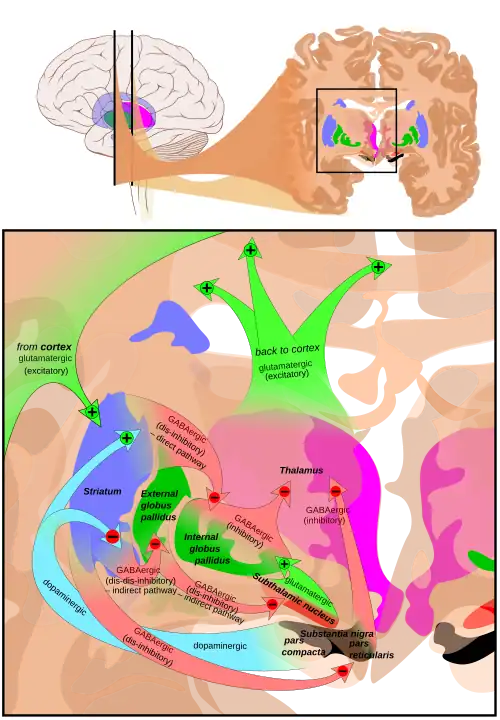

The substantia nigra (SN) is a basal ganglia structure located in the midbrain that plays an important role in reward and movement. Substantia nigra is Latin for "black substance", reflecting the fact that parts of the substantia nigra appear darker than neighboring areas due to high levels of neuromelanin in dopaminergic neurons.[1] Parkinson's disease is characterized by the loss of dopaminergic neurons in the substantia nigra pars compacta.[2]

Although the substantia nigra appears as a continuous band in brain sections, anatomical studies have found that it actually consists of two parts with very different connections and functions: the pars compacta (SNpc) and the pars reticulata (SNpr). The pars compacta serves mainly as a projection to the basal ganglia circuit, supplying the striatum with dopamine. The pars reticulata conveys signals from the basal ganglia to numerous other brain structures.[3]

Afferent connections

The main input to the SNpr derives from the striatum. It comes by two routes, known as the direct and indirect pathways. The direct pathway consists of axons from medium spiny cells in the striatum that project directly to pars reticulata. The indirect pathway consists of three links: a projection from striatal medium spiny cells to the external part of the globus pallidus; a GABAergic projection from the globus pallidus to the subthalamic nucleus, and a glutamatergic projection from the subthalamic nucleus to the pars reticulata.[6][7] Thus, striatal activity via the direct pathway exerts an inhibitory effect on neurons in the (SNpr) but an excitatory effect via the indirect pathway. The direct and indirect pathways originate from different subsets of striatal medium spiny cells: They are tightly intermingled, but express different types of dopamine receptors, as well as showing other neurochemical differences.

Significant projections occur to the thalamus (ventral lateral and ventral anterior nuclei), superior colliculus, and other caudal nuclei from the pars reticulata (the nigrothalamic pathway),[8] which use GABA as their neurotransmitter. In addition, these neurons form up to five collaterals that branch within both the pars compacta and pars reticulata, likely modulating dopaminergic activity in the pars compacta.[9]

The substantia nigra is an important player in brain function, in particular, in eye movement, motor planning, reward-seeking, learning, and addiction. Many of the substantia nigra's effects are mediated through the striatum. The nigral dopaminergic input to the striatum via the nigrostriatal pathway is intimately linked with the striatum's function.[10] The co-dependence between the striatum and substantia nigra can be seen in this way: when the substantia nigra is electrically stimulated, no movement occurs; however, the symptoms of nigral degeneration due to Parkinson's is a poignant example of the substantia nigra's influence on movement. In addition to striatum-mediated functions, the substantia nigra also serves as a major source of GABAergic inhibition to various brain targets.

Pars reticulata

The pars reticulata of the substantia nigra is an important processing center in the basal ganglia. The GABAergic neurons in the pars reticulata convey the final processed signals of the basal ganglia to the thalamus and superior colliculus. In addition, the pars reticulata also inhibits dopaminergic activity in the pars compacta via axon collaterals, although the functional organization of these connections remains unclear.

The GABAergic neurons of the pars reticulata spontaneously fire action potentials. In rats, the frequency of action potentials is roughly 25 Hz.[11] The purpose of these spontaneous action potentials is to inhibit targets of the basal ganglia, and decreases in inhibition are associated with movement.[12] The subthalamic nucleus gives excitatory input that modulates the rate of firing of these spontaneous action potentials. However, lesion of the subthalamic nucleus leads to only a 20% decrease in pars reticulata firing rate, suggesting that the generation of action potentials in the pars reticulata is largely autonomous,[13] as exemplified by the pars reticulata's role in saccadic eye movement. A group of GABAergic neurons from the pars reticulata projects to the superior colliculus, exhibiting a high level of sustained inhibitory activity.[14] Projections from the caudate nucleus to the superior colliculus also modulate saccadic eye movement. Altered patterns of pars reticulata firing such as single-spike or burst firing are found in Parkinson's disease[15] and epilepsy.[16]

Pars compacta

The most prominent function of the pars compacta is motor control,[17] though the substantia nigra's role in motor control is indirect; electrical stimulation of the substantia nigra does not result in movement, due to mediation of the striatum in the nigral influence of movement. The pars compacta sends excitatory input to the striatum via D1 pathway that excites and activates the striatum, resulting in the release of GABA onto the globus pallidus to inhibit its inhibitory effects on the thalamic nucleus. This causes the thalamocortical pathways to become excited and transmits motor neuron signals to the cerebral cortex to allow the initiation of movement, which is absent in Parkinson's disease. However, lack of pars compacta neurons has a large influence on movement, as evidenced by the symptoms of Parkinson's. The motor role of the pars compacta may involve fine motor control, as has been confirmed in animal models with lesions in that region.[18]

The pars compacta is heavily involved in learned responses to stimuli. In primates, dopaminergic neuron activity increases in the nigrostriatal pathway when a new stimulus is presented.[19] Dopaminergic activity decreases with repeated stimulus presentation.[19] However, behaviorally significant stimulus presentation (i.e. rewards) continues to activate dopaminergic neurons in the substantia nigra pars compacta. Dopaminergic projections from the ventral tegmental area (bottom part of the "midbrain" or mesencephalon) to the prefrontal cortex (mesocortical pathway) and to the nucleus accumbens (mesolimbic pathway – "meso" referring to "from the mesencephalon"... specifically the ventral tegmental area) are implicated in reward, pleasure, and addictive behavior. The pars compacta is also important in spatial learning, the observations about one's environment and location in space. Lesions in the pars compacta lead to learning deficits in repeating identical movements,[20] and some studies point to its involvement in a dorsal striatal-dependent, response-based memory system that functions relatively independent of the hippocampus, which is traditionally believed to subserve spatial or episodic-like memory functions.[21]